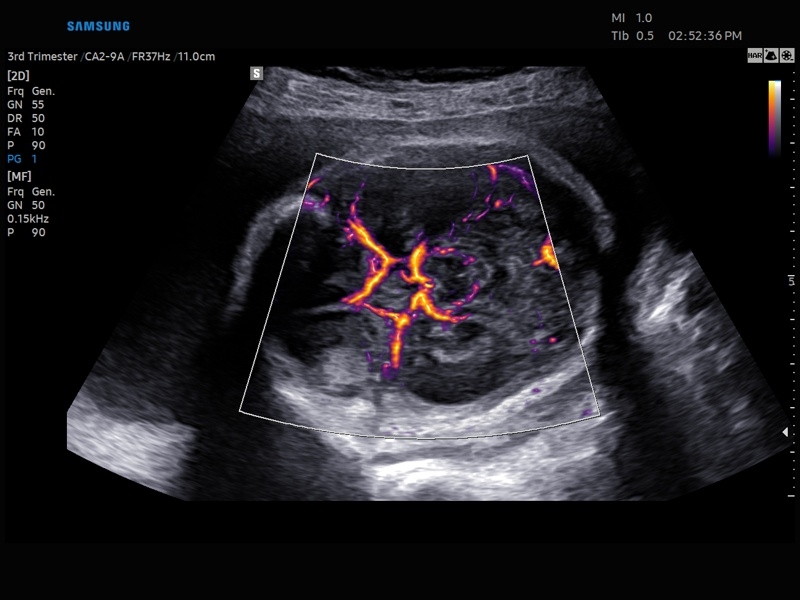

• Акушерство и гинекология

• Модуль MV-Flow – программа (режим), позволяющая визуализировать кровоток в микроциркуляторном русле с высоким разрешением без использования контраста.

• Модуль LumiFlow – программа отображения кровотока с объемной графикой для лучшего понимания архитектоники сосудистого русла.